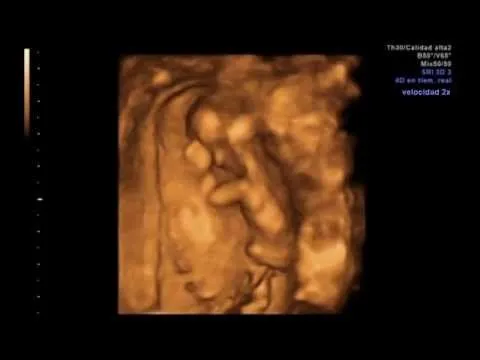

Los 9 meses del feto IMAGENES

Este album de Los 9 meses del feto IMAGENES con 5 fotos e imágenes no tiene descripción. Puedes sugerir una descripción de éste álbum y publicar nuevas fotos en él.